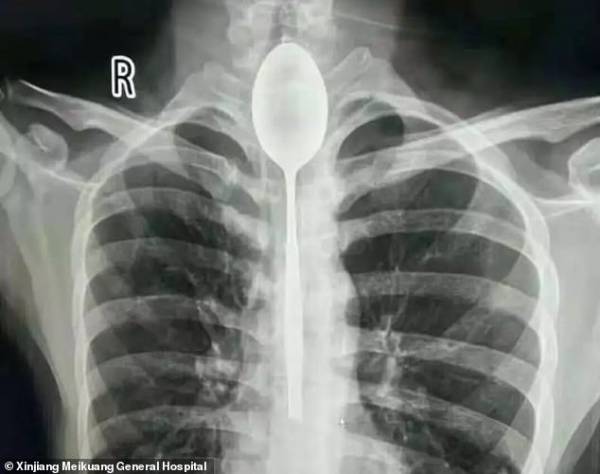

قورت دادن قاشق 20 سانتی سر شرط بندی + تصاویر

مرد چینی قاشق فلزی 8 اینچی را به عنوان یک شیرین کاری احمقانه در سال گذشته بلعید. قاشق در مری او گیر کرد، اما چون به راحتی می توانست بخورد و بنوشد، هرگز به دنبال کمک پزشکی برای بیرون آوردن آن نبود. او می گوید تنها چند روز پیش به علت ضربه وارد شده به قفسه سینه ، دچار درد قفسه سینه شد ؛ این جملات قسمتی از ماجرای عجیبی بود که در این بخش از سرگرمی نمناک خواهید خواند.

مردی که نامش فاش نشده است از منطقه جین جیانگ چین به پزشکان گفت :او یک قاشق فولادی ضد زنگ را در طی یک شرط درحالت مستی بلعیده . او به دوستانش گفته که می تواند قاشق را ببلعد و بعد دوباره با ریسمانی که به دسته قاشق می بندد آن را بیرون آورد . در آن زمان برای او حتما فکر خوبی به نظر می رسید، اما همه چیز طبق برنامه پیش نرفت و قاشق در گلوی او گیر کرد. به جای رفتن به بیمارستان، مرد منتظر ماند تا ببیند آیا قاشق به طور عادی از خوردن و نوشیدن جلوگیری می کند یا نه ؛ این طور نبود، پس در مری ماند تا سال گذشته.

قاشق مدت طولانی در سینه او مانده بود و براثر ضربه ای که به سینه او وارد شده بود باعث درد شدید و تنفس بدبو او شده بود . سرانجام به بیمارستان عمومی جین جیانگ رفت و به پزشکان گفت یک سال است که قاشق فلزی در مری او گیر کرده است.

پزشکان در بیمارستان عمومی جین جیانگ پس از بحث در مورد بهترین مسیر عمل تصمیم گرفتند که بهترین راه خارج کردن قاشق ، از طریق دهان بوده است. داروی بی هوشی به بیمار دادند و یک تیم دو ساعت تلاش کردند تا با استفاده از تجهیزات آندوسکوپی ، قاشق 8 اینچی را بیرون آوردند.